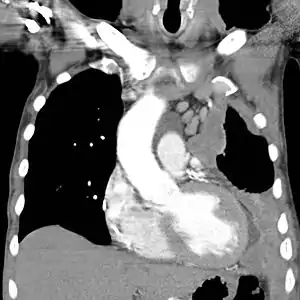

Diagnosing mesothelioma is often difficult because the symptoms are similar to those of a number of other conditions. Diagnosis begins with a review of the patient's medical history. A history of exposure to asbestos may increase clinical suspicion for mesothelioma. A physical examination is performed, followed by chest X-ray and often lung function tests. The X-ray may reveal pleural thickening commonly seen after asbestos exposure and increases suspicion of mesothelioma.[15] A CT (or CAT) scan or an MRI is usually performed. If a large amount of fluid is present, abnormal cells may be detected by cytopathology if this fluid is aspirated with a syringe.[11] For pleural fluid, this is done by thoracentesis or tube thoracostomy (chest tube); for ascites, with paracentesis or ascitic drain; and for pericardial effusion with pericardiocentesis. While absence of malignant cells on cytology does not completely exclude mesothelioma, it makes it much more unlikely, especially if an alternative diagnosis can be made (e.g., tuberculosis, heart failure). However, with primary pericardial mesothelioma, pericardial fluid may not contain malignant cells and a tissue biopsy is more useful in diagnosis.[11] Using conventional cytology diagnosis of malignant mesothelioma is difficult, but immunohistochemistry has greatly enhanced the accuracy of cytology.